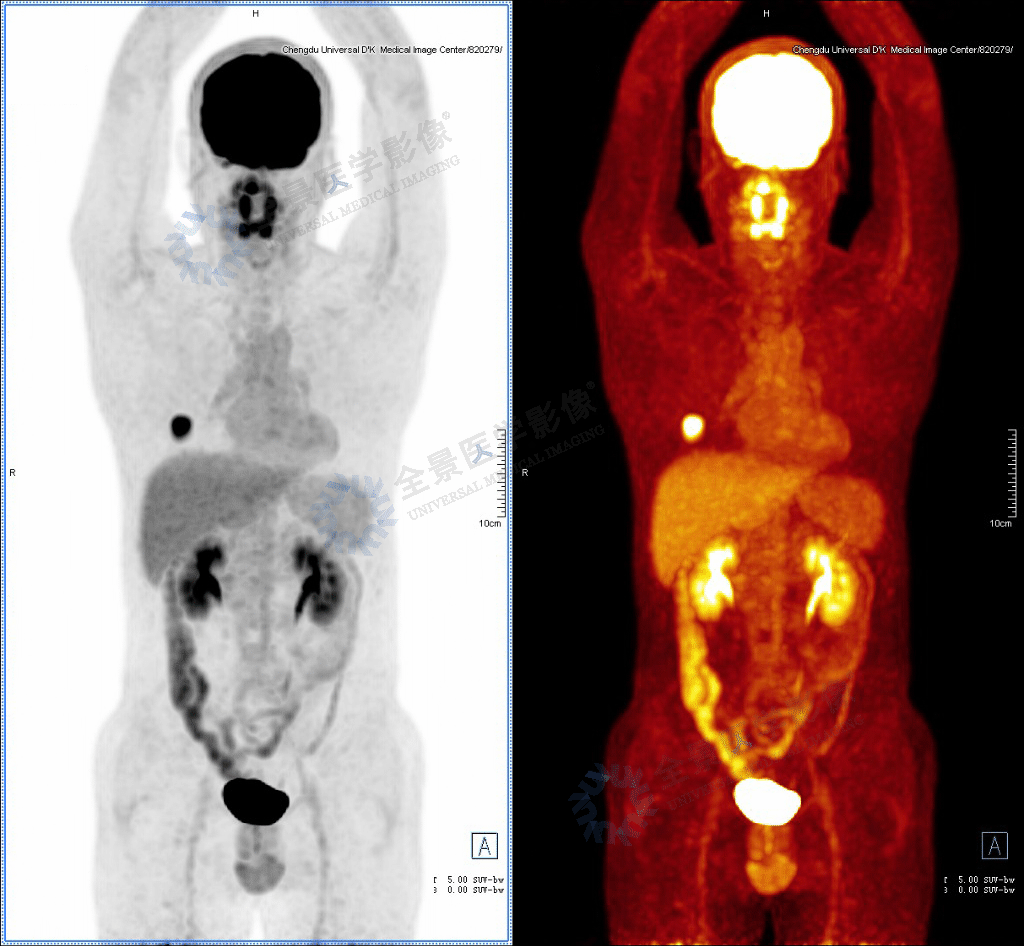

34岁的周先生(化名),已有6-7年吸烟史,平均10支/日,偶有社交饮酒。3年前体检行胸部CT检查,报告为“双肺未见明显异常”。 2025年,周先生再次进行体检。此次胸部CT检查发现“右肺下叶外基底段实性结节灶”。由于结节为新发现,且周先生自述偶有心前区不适症状(检查基本已排除心脏器质性疾病),为明确肺结节性质,医生建议行进一步检查。随即,周先生接受了18F-FDG PET/CT检查。 PET/CT全身检查图像: PET/CT检查示: 右肺下叶外基底段见一含囊腔的结节,大小约2.6cm ×2.3cm ×2.6cm,其下份呈实性密度,前上份可见直径约1.5cm含气囊腔,病变边缘可见分叶,边界清,邻近支气管未见明确闭塞,实性部分FDG摄取增高,SUVmax9.8,病变周围见少许磨玻璃晕征。影像诊断高度提示为肿瘤性病变。 基于PET/CT的强烈提示,周先生接受了右肺下叶结节切除术。术后组织病理学检查最终确诊为“浸润性非黏液腺癌” 。 病理结果: 景哥提醒 本病例虽发生在年轻男性身上,但其完整的诊疗链条清晰地揭示了肺癌早期发现的几个关键环节,具有深刻的警示和教育意义。 (1) 定期体检的重要性:胸部CT可发现早期肺结节,为干预争取时间,若患者未坚持体检,可能错过早期干预的最佳时机。 (2) PET/CT的代谢诊断优势:通过FDG代谢活性分析,显著提高肺结节的定性准确性,而且还排除了远处转移,为后续手术方案的制定提供了关键依据。 (3) 个体化管理的必要性:结合患者风险因素、影像特征及病理结果,制定精准诊疗方案。 高危人群的筛查策略: 年龄≥40岁(Ⅱ类推荐),且具有下述任一危险因素者[1]: (1)吸烟指数≥400年支(或20包年)(ⅠA类推荐); (2)环境或高危职业暴露史(如石棉、铍、铀、氡等接触者)(ⅠB类推荐); (3)合并慢阻肺、弥漫性肺纤维化或曾患肺结核者(ⅠB类推荐); (4)曾患恶性肿瘤或有肺癌家族史者,尤其一级亲属家族史(ⅠB类推荐)。 推荐每年采用胸部LDCT对肺癌高危人群进行筛查,发现结节后每3-6个月复查[1]。 对于不能定性的直径>8 mm的实性肺结节可考虑采用PET/CT区分良恶性[1]。 参考文献: [1] 中国肺结节诊治专家共识2024版 说明:*以上内容未经作者及相关权利人许可,不得商用。 *文中案例为全景所有,未经允许不得转载,盗用必究! 作者简介: 审核医师: